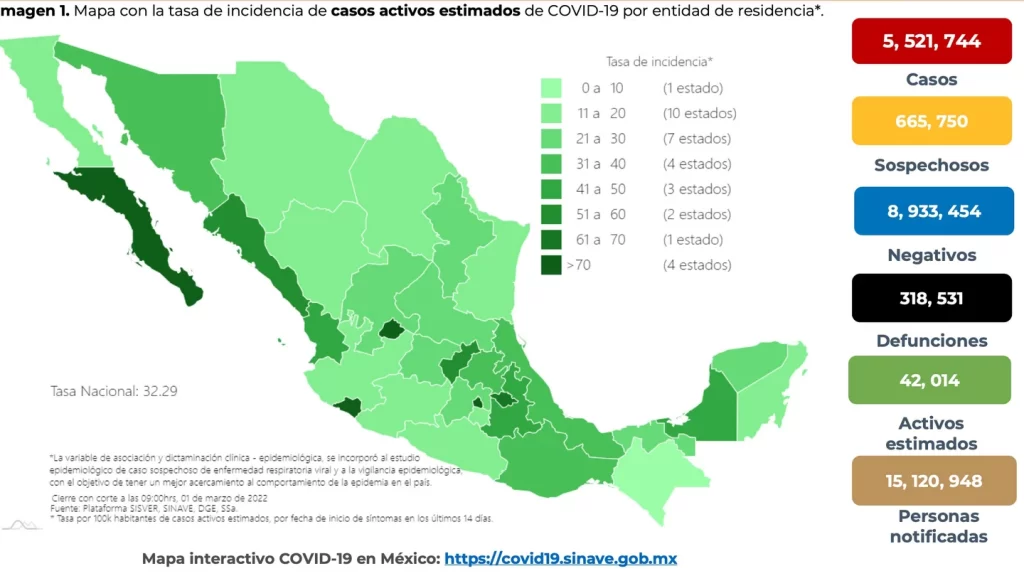

Reporta SSO 22 nuevos casos de COVID-19 en Oaxaca

Los Servicios de Salud de Oaxaca (SSO) reportaron 22 nuevos casos de COVID-19 en la última semana, con un acumulado de 98 casos confirmados en lo que va del año 2025,